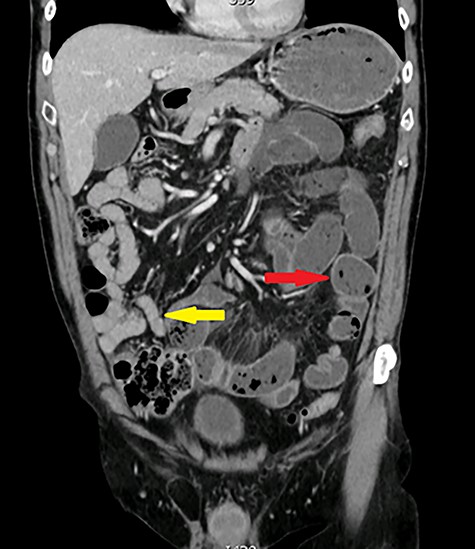

One year later, he was readmitted with small bowel obstruction investigated with an abdominal computed tomography (CT) scan that showed no radiological finding of stenotic Crohn disease or other obstructive etiology (Figs 2 and 3).

Axial view: arrows pointing to dilated and collapsed small bowel.

Coronal view: arrows pointing to dilated and collapsed small bowel.

CT scan and endoscopic techniques are commonly used in preoperative diagnosis; however, CT scanning tends to lack the resolution required to highlight the SBD and generally do not show any abnormal results when used to explore chronic abdominal pain, and it could advocate for small bowel acute strangulation on adhesions when used to explore acute small bowel occlusion [8–10]. In regards to capsule enteroscopy, it should only be undertaken on patients with iron-deficiency anemia with no obstructive symptoms, to prevent the risk of capsule retention [3–6].